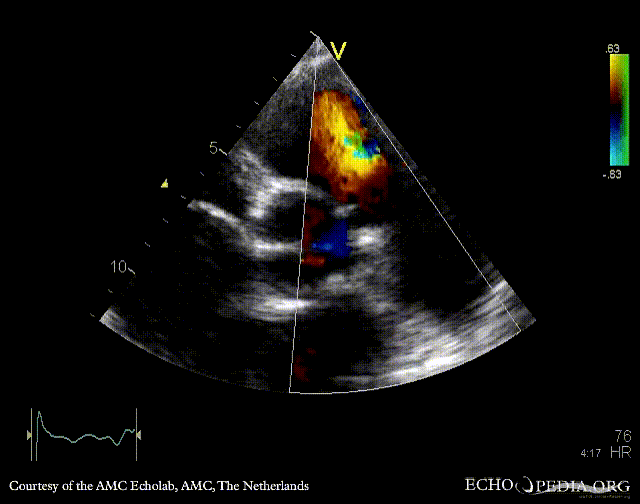

E00433.gif E00434.gif

PSAX: thickend aortic valve PLAX: severe aortic and mitral regurgitation